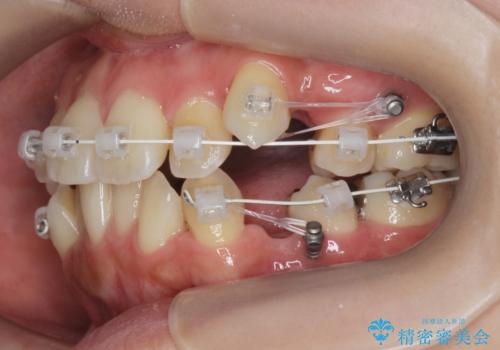

八重歯を矯正治療で治したい!

- 八重歯・がたつきのある歯並びの改善を求めて来院されました。

全部の歯が入り切るスペースがなかったため、小臼歯4本を抜去しワイヤーを用いたマルチブラケット矯正を選択しました。

歯並びの改善と共に、歯ブラシがしやすくなった!と喜んでいただくことができました。